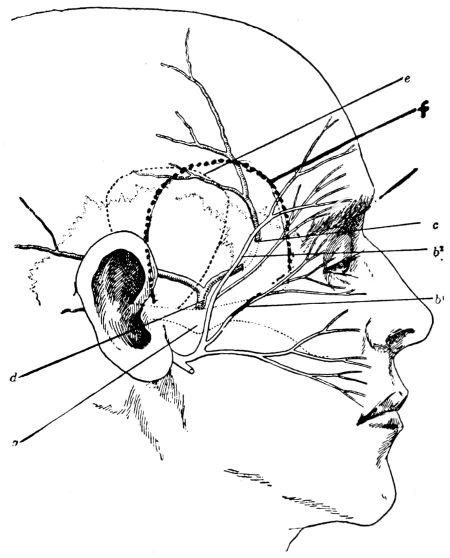

| 1 and 2. Cranio-cerebral topography | 2, 3 |

Fig. 1. Cranio-cerebral Topography. 1, The nasion; 2, The inion; 3, The mid-point between nasion and inion; 4, The Rolandic fissure; 5, The superior temporal crest; 6, The inferior temporal crest; 7, The Sylvian point; 8, The anterior horizontal limb of the Sylvian fissure; 9, The vertical limb of the Sylvian fissure; 10, The posterior horizontal limb of the Sylvian fissure; 11, The parietal prominence; 12, The malar tubercle; 13, The lambda; 14, The first temporo-sphenoidal sulcus; 15, The external parieto-occipital sulcus; 16, The lateral sinus; 17, 17, 17, The level of the base of the cerebrum; 18, The external auditory meatus; 19, 19, Reid’s base-line. (Reproduced, by the permission of Mr. H. K. Lewis, from the author’s work on ‘Landmarks and Surface-markings’.)

Fig. 2. Cranio-cerebral Topography. 1, 1, Reid’s base-line; 2, 2, A line parallel to the above at the level of the supra-orbital margin; 3, The middle meningeal artery; 4, The anterior branch; 5, 5, 5, The three sites for trephining; 6, The posterior branch; 7, The site for trephining; 8, The point for trephining to reach the descending horn of the lateral ventricle; 9, The lateral sinus; 10, The inion; 11, The mastoid process; 12, Macewen’s suprameatal triangle; 12a, The mastoid antrum; 12b, The facial nerve; 13, The suprameatal and supramastoid crests; 14, 14, The temporal crest; 15, The temporal fossa; 16, The external angular frontal process; 17, The tendo-oculi attachment; 18, The lachrymal groove. (Reproduced, by the permission of Mr. H. K. Lewis, from the author’s work on ‘Landmarks and Surface-markings’.)

Firstly, the skull can be divided into two lateral halves by the surface-marking of the superior longitudinal venous sinus.

This sinus originates at the crista galli and, passing backwards along the attached margin of the falx cerebri, terminates at the internal occipital protuberance. It may be represented by a line drawn from the base of the nose (the nasion), over the vertex of the skull, to the external occipital protuberance (the inion)—this line corresponding in its course to the occasionally persistent metopic suture between the two halves of the frontal bone, to the sagittal suture between the parietal bones, and to the middle line of the upper or tabular portion of the occipital bone.

Secondly, each lateral half of the skull can be subdivided into supra- and infratentorial regions by a line which marks the external attachment of the tentorium cerebelli; in other words, by the line of the lateral sinus.

This sinus is represented by a line presenting a slight upward convexity, which is drawn from the external occipital protuberance to the upper and posterior part of the mastoid process of the temporal bone.

These landmarks having been determined, the following structures may be mapped out on the surface of the skull.

This artery is given off from the internal maxillary; after a short extra-cranial course it enters the skull through the foramen spinosum, and soon divides into two main terminal branches. The site of division corresponds to a point situated just above the centre of the zygoma.

The anterior branch passes at first in a forward and upward direction towards the anterior inferior angle of the parietal bone, and then turns upwards and backwards towards the vertex of the skull. The main ‘danger zone’ in the course of this vessel may be mapped out by taking points which lie respectively 1, 11⁄2, and 2 inches behind the external angular frontal process and an equal distance above the upper border of the zygoma. A line uniting these three points represents that part of the anterior division of the middle meningeal artery which is most liable to injury and which therefore most frequently requires exposure.

The uppermost point may, however, be regarded as the ‘site of election’ for exposure of the artery, as, in trephining over either of the two lower points, difficulty may be experienced in the removal of the disk of bone, since the posterior border of the great wing of the sphenoid tails off on to the anterior inferior angle of the parietal bone in such a manner that to effect a clean removal of the disk is often impossible. Another disadvantage to trephining low down lies in the fact that in about 30 to 40 per cent. of cases the artery occupies, in that situation, a canal in the bone.

The posterior branch passes almost horizontally backwards, parallel to the zygoma and supramastoid crest, towards the posterior inferior angle of the parietal bone. The vessel can readily be exposed[6] by trephining over the point at which a line drawn backwards from the upper border of the orbit, parallel to Reid’s base-line,[1] cuts another line directed vertically upwards from the posterior border of the mastoid process.

Both branches of the middle meningeal artery possess important relations to the cortex cerebri, the anterior branch passing upwards in relation to the precentral or motor area, traversing, from below upwards, the motor speech area (on the left side of the head), the centres for the movements of the face, upper extremity, trunk, and lower extremity. The posterior branch, on the other hand, passes backwards in relation to the temporo-sphenoidal lobe, one of the so-called ‘silent areas’ of the brain. Throughout their course the middle meningeal vessels lie between the dura mater and the bone.

The lower limit of the cerebrum can be mapped out in the following manner: From a point situated about 1⁄2 inch above the nasion a line is drawn outwards which follows the curve of the upper border of the orbit as far as the external angular frontal process, thence curving upwards and backwards to the Sylvian point (see below). The temporo-sphenoidal lobe sweeps forwards to the posterior border of the malar bone, and its lower limit lies practically flush with the upper margin of the zygoma. At and behind the ear the lower limit of the cerebrum corresponds to the suprameatal and supramastoid crests, subsequently following the curve of the lateral sinus from the mastoid process to the external occipital protuberance.

The Sylvian point represents the site of divergence of the three limbs of the Sylvian fissure. It lies 11⁄4 inches behind the malar tubercle and 11⁄2 inches above the upper border of the zygoma. The main posterior horizontal limb passes backwards and upwards to a second point situated 3⁄4 inch below the parietal prominence.

The vertical limb is directed upwards for about 1 inch, whilst the anterior horizontal limb passes forwards for about the same distance.

This, from a surgical point of view,[7] the most important fissure of the brain, is represented as follows: A point is taken in the median antero-posterior line which lies 1⁄2 inch behind the mid-point between nasion and inion, and from this point a line is drawn, for 31⁄2 to 4 inches, towards the mid-point of the zygoma. This line is inclined to the median antero-posterior line at an angle of 671⁄2° (three-quarters of a right angle).

In the representation of these two fissures, two points require to be determined—the malar tubercle and the lambda. Allusion has already been made to the former; the latter is usually readily located as the point of intersection of the sagittal and lambdoid sutures. A line uniting these two points corresponds in its middle third to the temporo-sphenoidal fissure, and in its posterior inch or so to the external parieto-occipital sulcus, a fissure separating the occipital and parietal lobes of the brain.

The researches of Sherrington and Grünbaum,[2] Campbell,[3] and others tend to show that the cortical motor areas are situated entirely anterior to the central fissure or fissure of Rolando, extending above well over on to the mesial aspect of the brain, though not so far as the calloso-marginal fissure, and in the downward direction to within a short distance of the fissure of Sylvius. In the posterior direction the motor area includes the anterior boundary and part of the bottom of the fissure of Rolando, whilst in front it spreads, by means of gyri annectantes, on to that part of the brain which lies anterior to the precentral sulcus. The anterior termination is indefinite, but the motor strip is, on an average, not more than 3⁄4 inch in breadth.

This motor strip corresponds, from above downwards, to the movements of the contralateral lower extremity (toe to hip), trunk, upper extremity (shoulder to fingers), neck and face. It is a point of some general utility to bear in mind that the temporal crest intervenes approximately between the regions responsible for the movements of the upper extremity (above the crest) and those for the movements of the head and face (below the crest).

Fig. 3. The Cortical Motor and Sensory Areas.

On the left side of the head—in normal right-handed individuals—the motor speech area of Broca corresponds to the third left frontal convolution, in the angle between the anterior and posterior horizontal limbs of the Sylvian fissure.

The ‘primary registration’ of ‘common sensation’ occurs in the post-central gyrus, immediately posterior to the fissure of Rolando. This tactile area occupies a position behind the fissure of Rolando[9] similar in extent to that occupied by the motor area in front. It commences at the bottom of the fissure of Rolando and extends backwards over rather more than half the exposed area of the post-central convolution. It reaches down to near the Sylvian fissure and extends over on to the mesial aspect of the brain. Furthermore, it is probable that sensation in any given part lies on more or less the same level as the corresponding motor area.

Immediately posterior to the tactile area and occupying the posterior and upper part of the post-central convolution, the area responsible for muscle-sense is situated.

Stereognosis—memory pictures, object perception, &c.—is referred to the superior parietal lobe.

Primary visual impressions are received in the occipital lobe, more especially on the mesial aspect thereof.

Finally, the four areas concerned in speech—motor speech, writing, reading, and hearing—are anatomically separated from one another and yet closely associated, so much so that one can hardly be involved without the other. The motor speech centre of Broca has already been mentioned as occupying—in right-handed individuals—the posterior part of the third left frontal convolution. Writing lies immediately above and in front, in the posterior part of the middle frontal gyrus, auditory impressions are received in the posterior and upper part of the first temporo-sphenoidal lobe, whilst the power of reading is dependent on the integrity of the supramarginal and angular gyri (see also Fig. 57).

Smell and Taste lie in close relation to the anterior pole of the temporo-sphenoidal lobes.